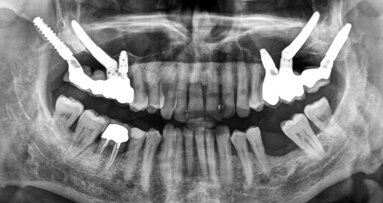

Rekonstrukce v dolní čelisti popsaná v následující kazuistice byla provedena pomocí ASTRA TECH Implant System® EV a konceptu SmartFix® (Dentsply ...